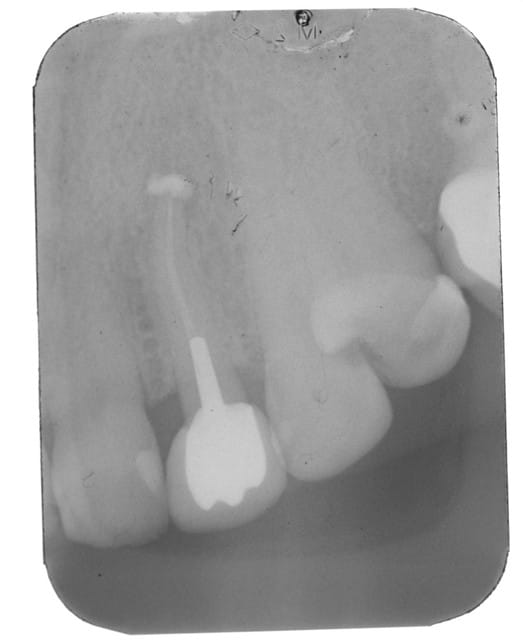

ci joint la radio de controle de l extraction reimplantation du cas de la page 11.

la reconstruction osseuse a l apex est evidente .

il n y a pas eu de provisoire sur cette dent et c est dommage .en effet il y a une migration en mesial et le ligament est lache .

faudrait faire la prothese au plus vite mais là c est une autre histoire.......financiere....